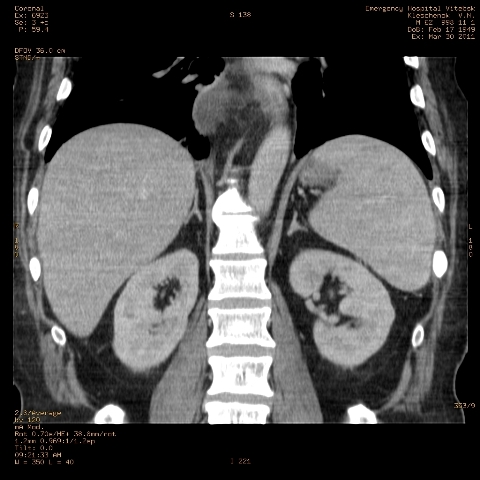

при исследовании органов брюшной полости по поводу абсцесса печени, в нижнем этаже средостения выявлено образование неоднородной плотности (-5-+25), при в/в контрастировании - не контрастируется, при per os - затёков из пищевода нет, неправильно овальной формы. предположительно киста перикарда? спасибо за помощь!

Может быть enteric duplication cyst. Как бы есть грыжа жира hiatal. И что с печенью? Мало срезов.